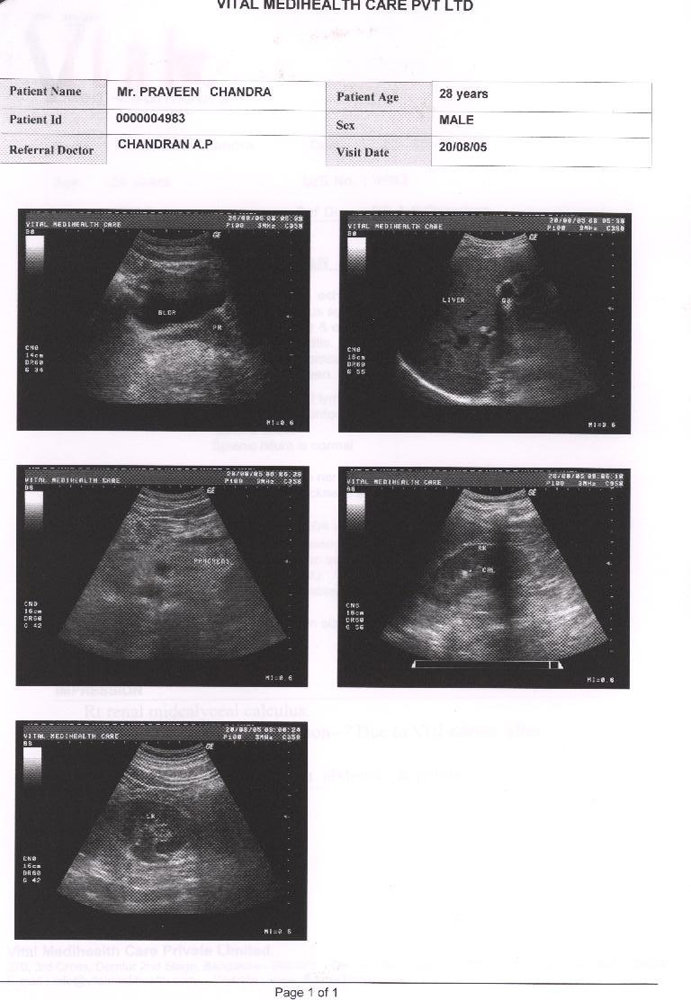

Condition of patient in after 25 days of taking Homoeopathic remedy